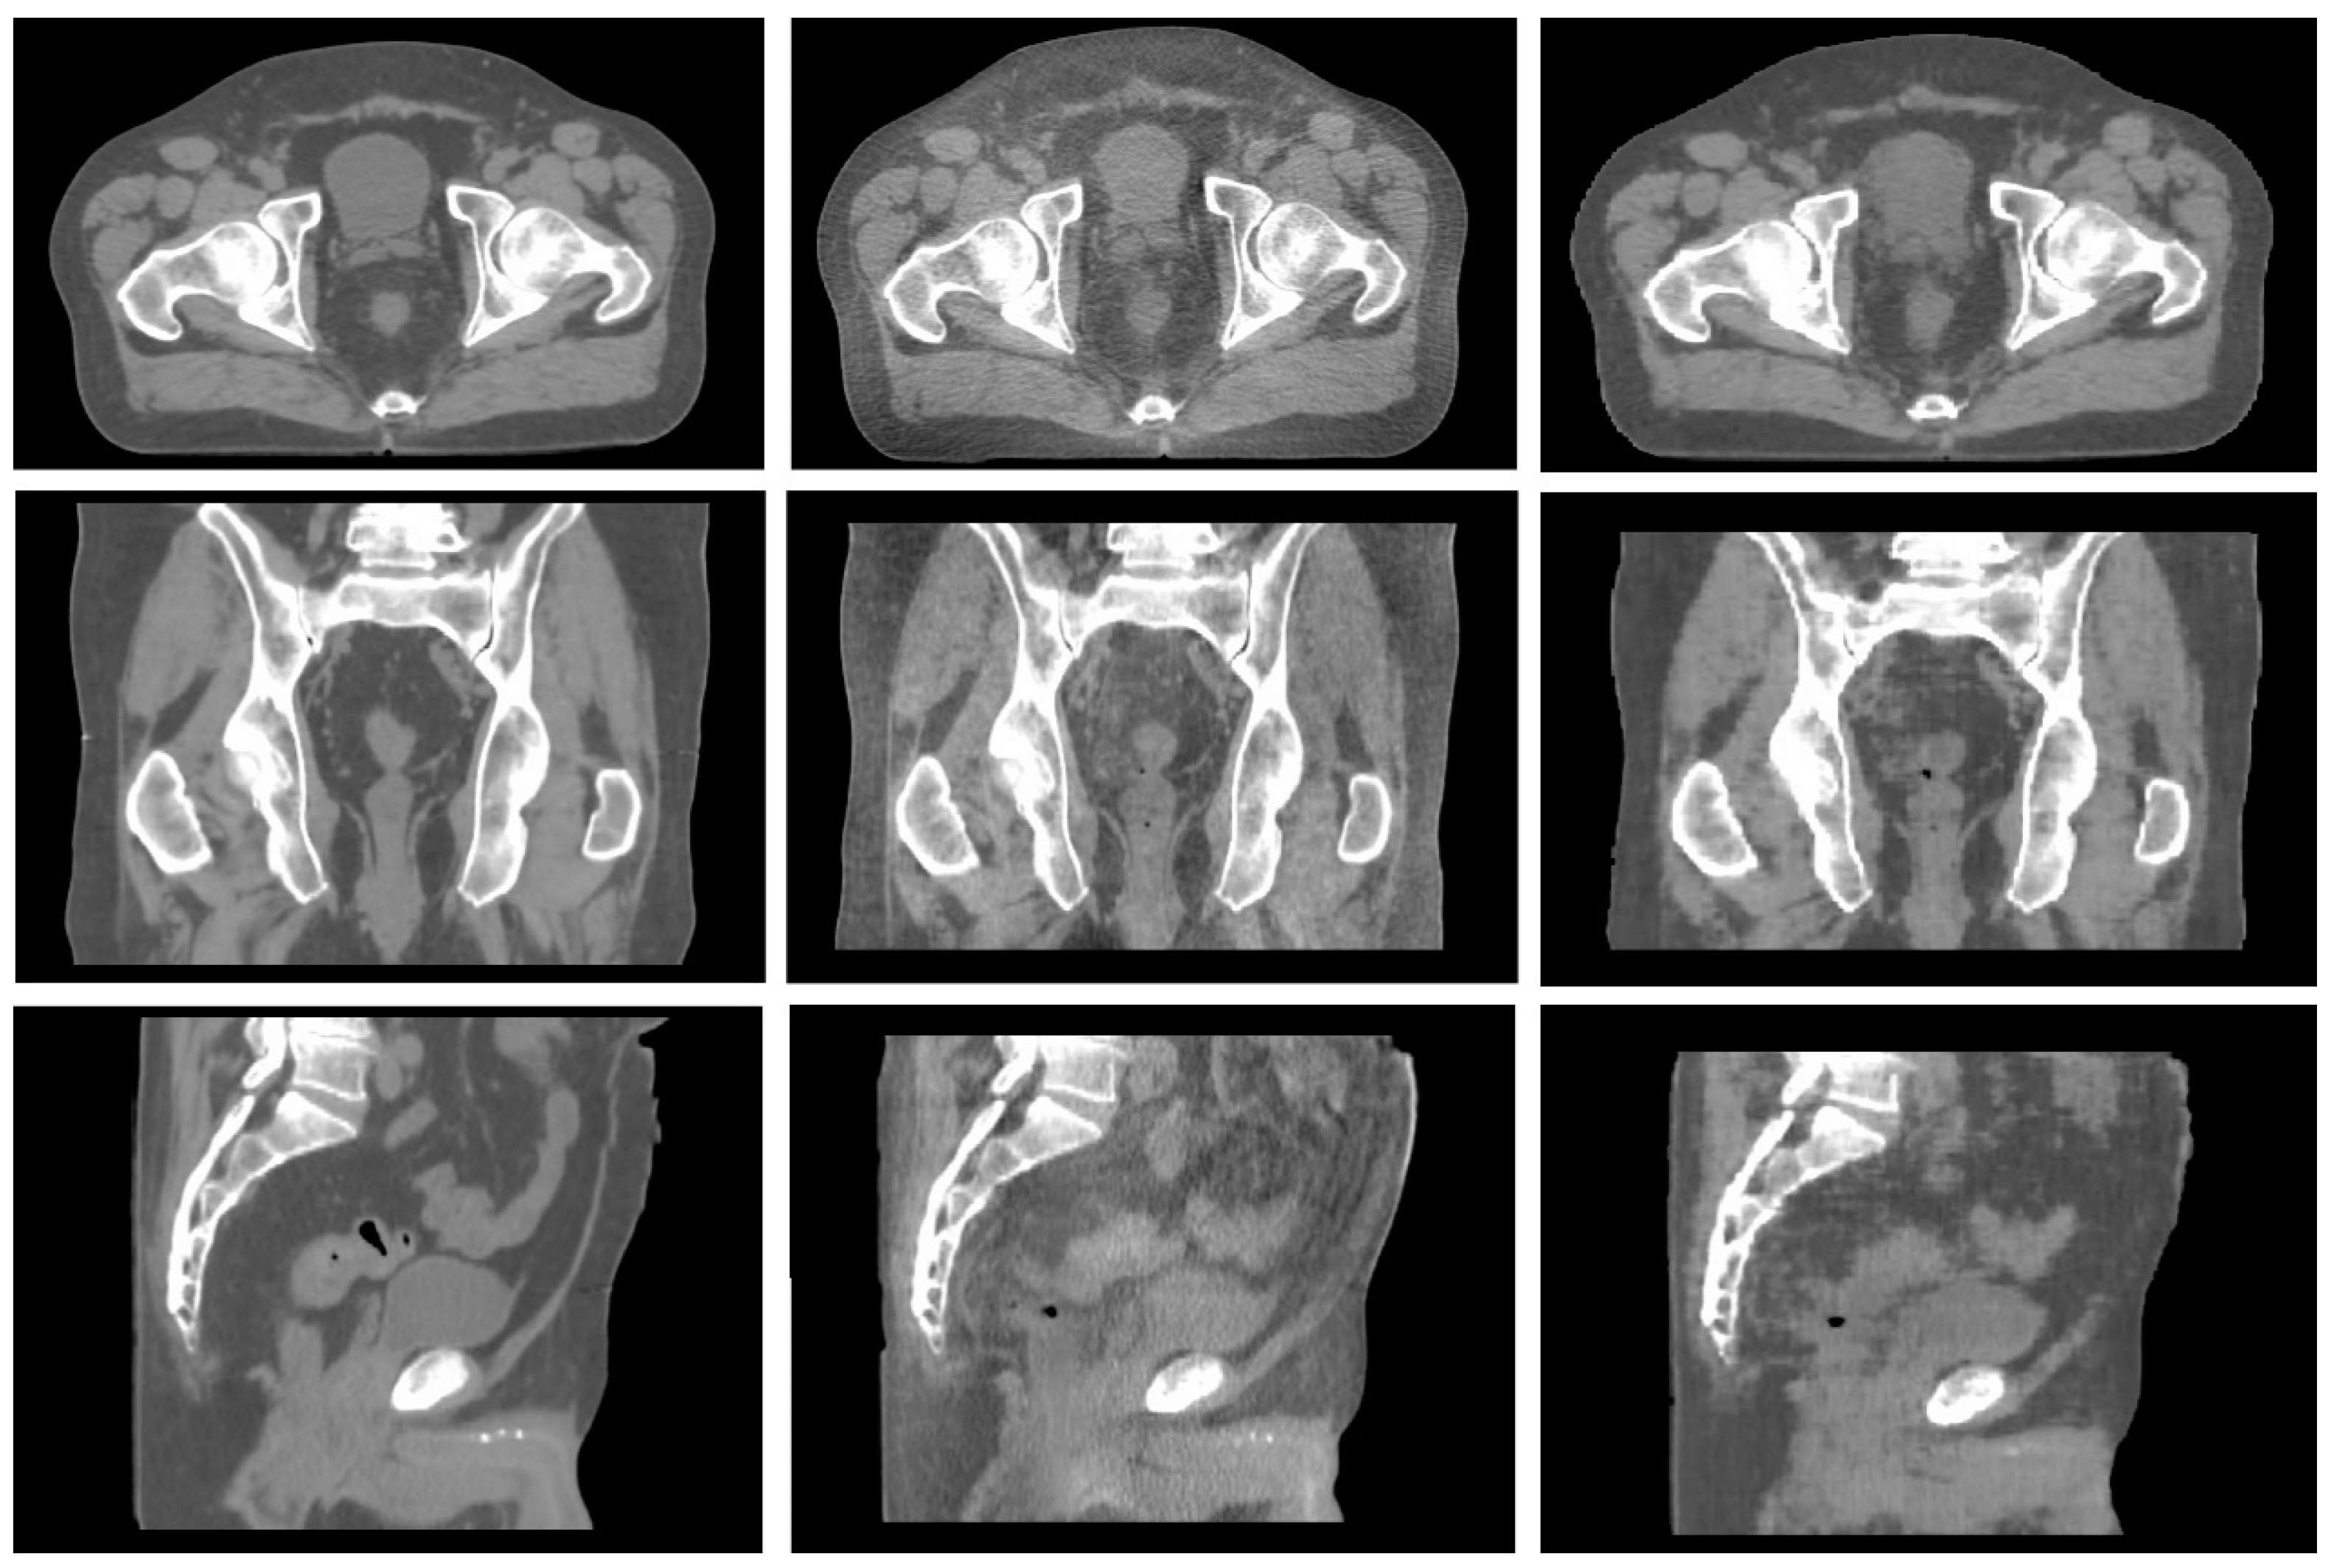

Each network training process took a mean of 24 h, while the mean generation time for a sCT study was 74 ± 7 s. The image selection process initially performed resulted in a discard of 3128 and a selection of 1379 paired images that met the image quality criteria. A learning rate of 2·10−4 and a lambda value of 2000 were identified as optimal hyperparameters set during network optimisation. Figure 1 reports a comparison between the sCT obtained using the optimal hyperparameter set and the corresponding CBCT and CT for a test patient chosen as an example.

Figure 1. Example of CT (left), CBCT (centre), and synthetic CT (right) generated in the axial, sagittal, and coronal planes in a pelvic case.